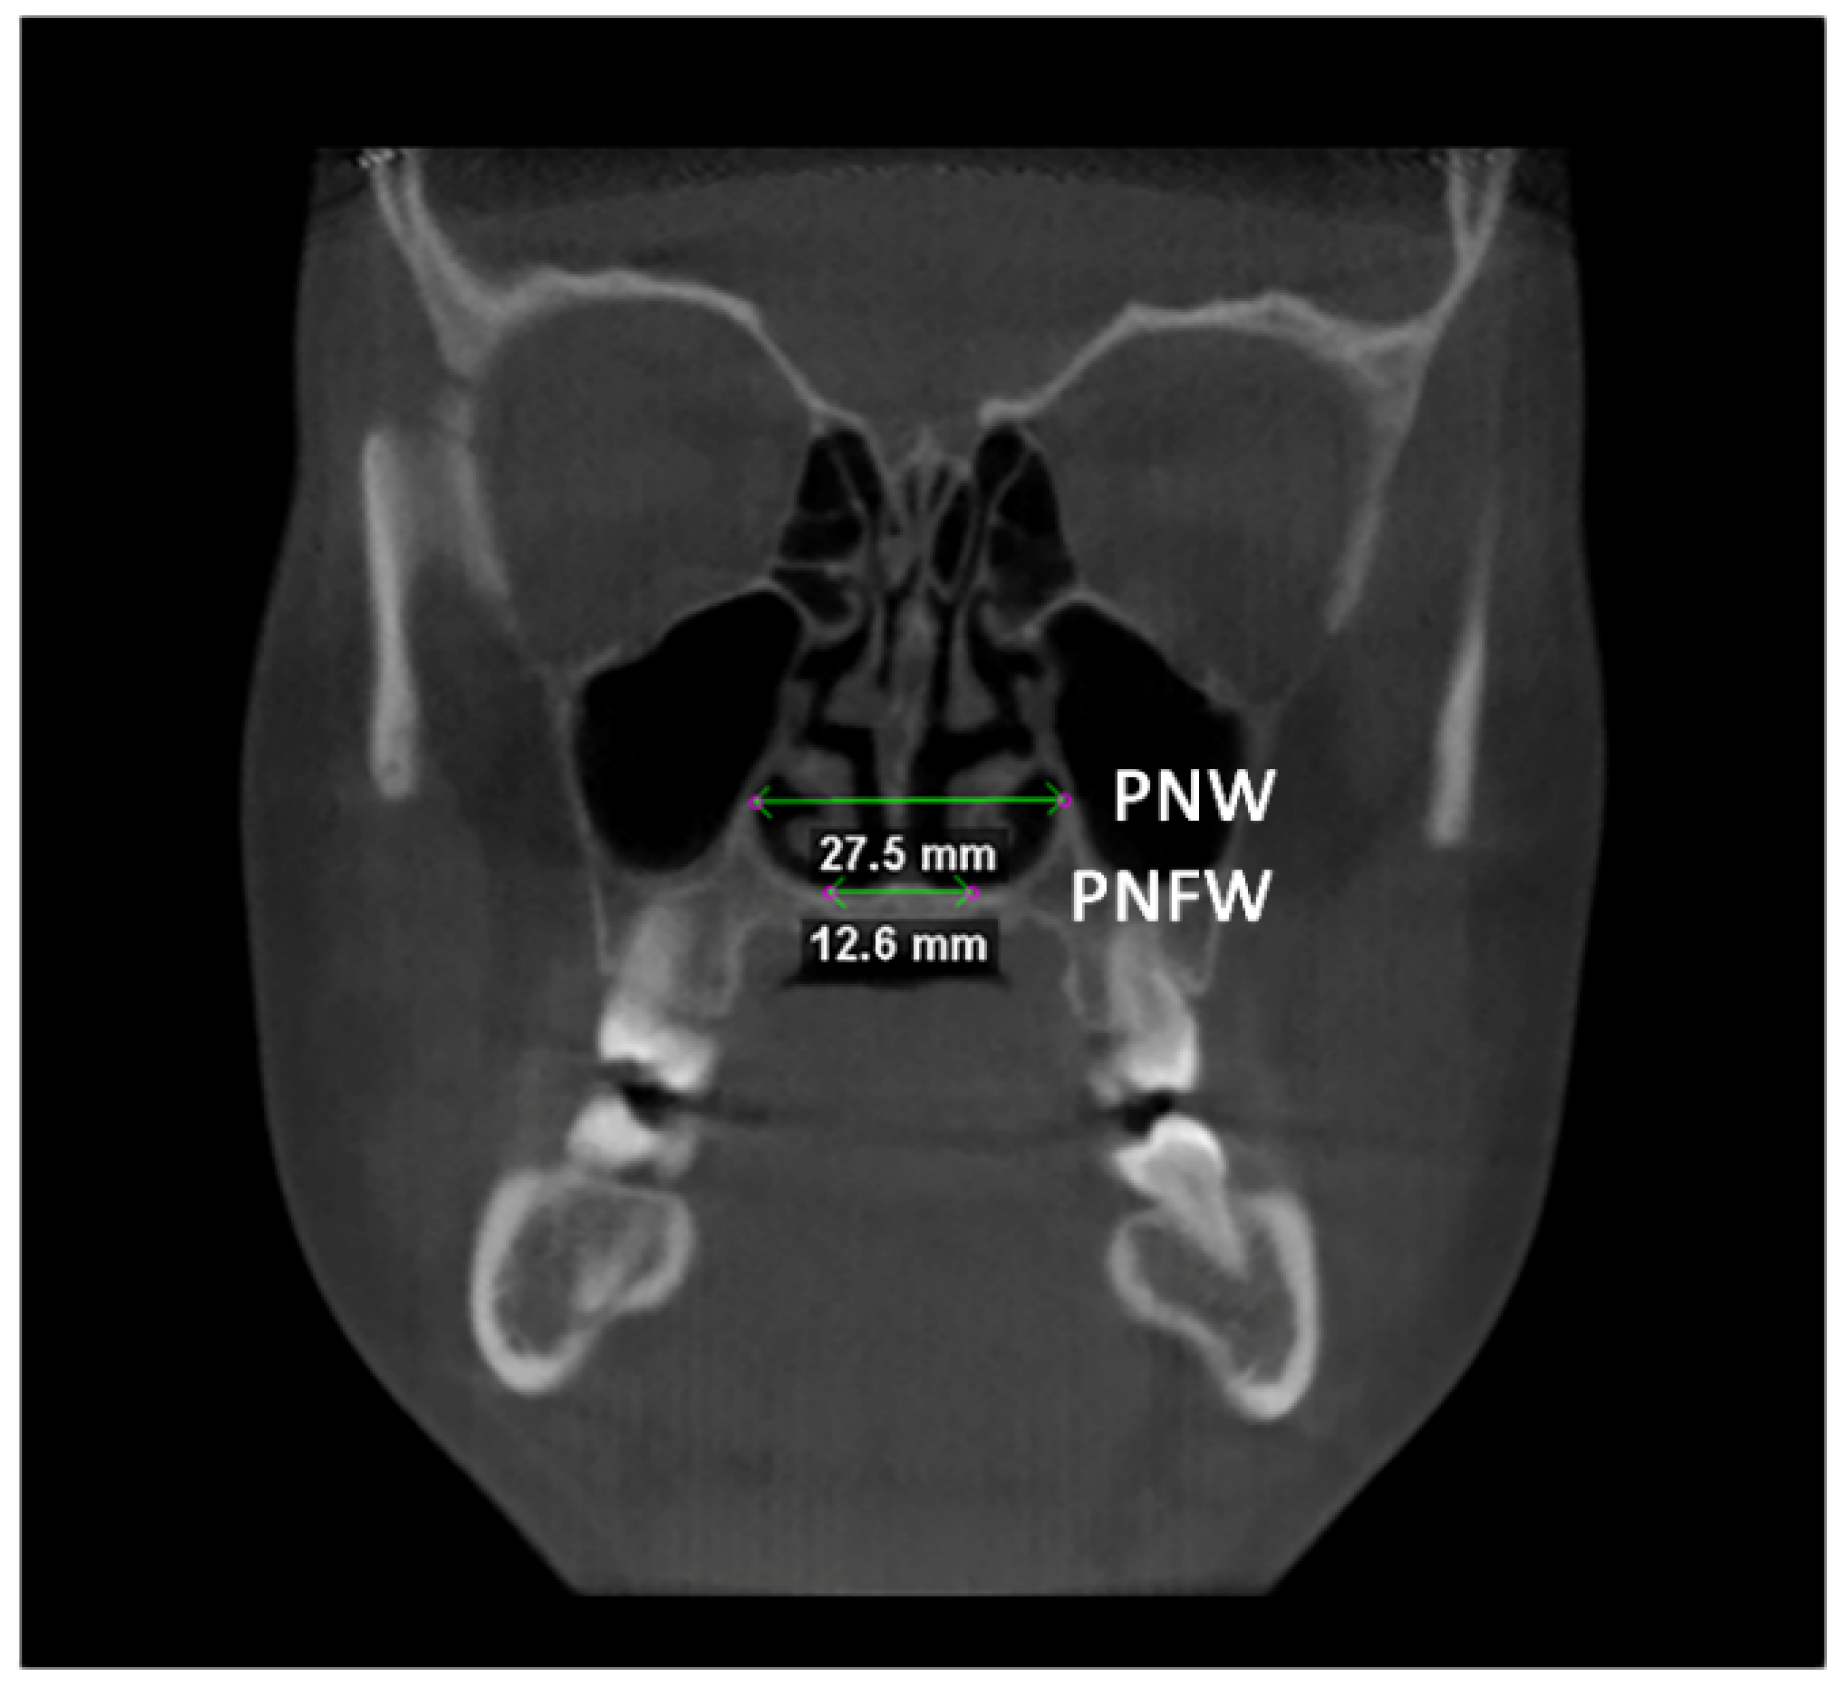

Afterward, the transverse dimension of the Apertura Piriformis was measured in the anterior and posterior regions. In the coronal plane passing through the cephalometric point N, the linear measurements of anterior nasal width (ANW) and anterior nasal floor width (ANFW) were performed (Figure 3, Table 1). Similarly, in the coronal plane passing through the upper margin of the mesial aspect of the Sella Turcica, the linear measurements of the posterior nasal width (PNW) and posterior nasal floor width (PNFW) were performed (Figure 4, Table 1). The entire procedure for skeletal measurements was performed by using the Dolphin 3D software (Dolphin Imaging, version 11.0, Chatsworth, CA, USA).

Figure 4.

Linear measurements of the posterior nasal width (PNW) and the posterior nasal floor width (PNFW) in the coronal plane.